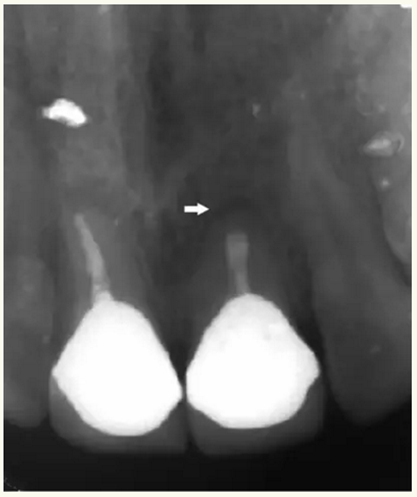

▲ 術(shù)前,21唇側(cè)牙齦距離齦緣2mm處及瘺管

▲牙膠尖示蹤顯示瘺管與此相通

▲21牙根近中側(cè)位于根尖1/3和根中1/3交界處有牙周膜間隙略增寬

▲術(shù)后,手術(shù)切口處疤痕

▲術(shù)后,X線顯示:21根尖切除區(qū)域骨質(zhì)修復(fù),根管倒充填物完好,原牙周膜間隙增寬影消失